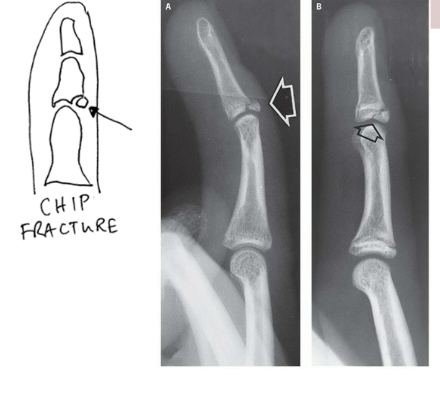

What type of fracture is this?

Chip

What is a chip fracture?

Isolated bone fragment NOT caused by tendon or ligament